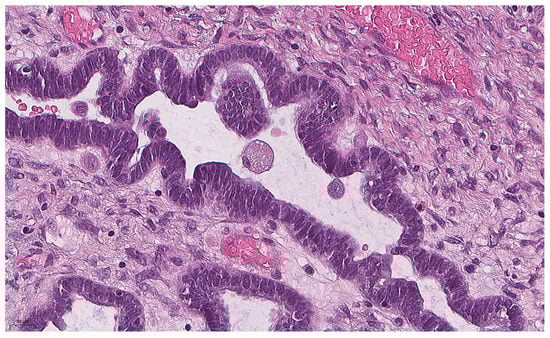

Eosinophilic Cells as a Distinct Morphological Feature in BRAFV600E-Mutated Ovarian Serous Borderline Tumors